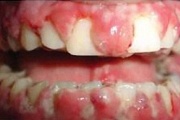

Krooniline gingiviit

ANUG (äge nekrotiseeruv haavandiline gingiviit/parodontiit)

Äge krooniline gingiviit

igemete veritsus kroonilise gingiviidiga patsiendil